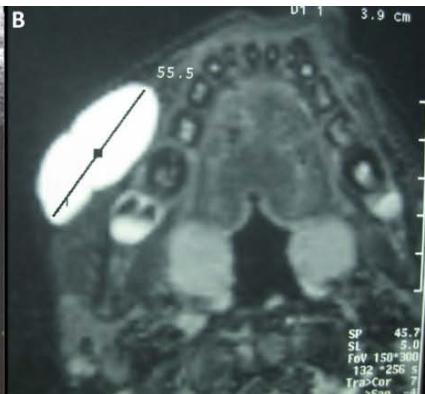

Figure/Patient 2

A case of right mandibular lymphangioma in a 10 year-old boy, hypoechoic with some septations and no blood vessels (A) and hyper-intense on T2 axial (B) and coronal (C) MR scans.